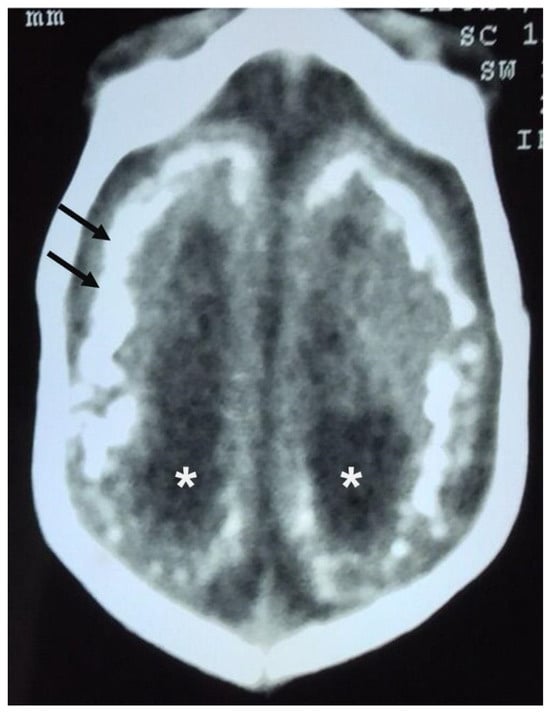

- Ribeiro, B.N.d.F.; Muniz, B.C.; Gasparetto, E.L.; Ventura, N.; Marchiori, E. Congenital Zika syndrome and neuroimaging findings: What do we know so far? Radiol. Bras. 2017, 50, 314–322. [Google Scholar] [CrossRef] [PubMed] [PubMed Central]

- Araujo Júnior, E.; Carvalho, F.H.; Tonni, G.; Werner, H. Prenatal imaging findings in fetal Zika virus infection. Curr. Opin. Obstet. Gynecol. 2017, 29, 95–105. [Google Scholar] [CrossRef] [PubMed]

| Findings | Computed Tomography | Magnetic Resonance Imaging |

|---|---|---|

| Microcephaly | Reduced skull diameter and brain volume | Reduced skull diameter and brain volume |

| Cerebellar hypoplasia | It can be observed | It can be observed |

| Cortical abnormalities | Can identify volumetric reduction in the brain parenchyma | Best examination to identify cortical abnormalities, usually diffuse and predominantly in the frontal lobes |

| Prominence of the occipital bone | Detected | Detected |

| Intracranial calcifications | Sensitive to calcifications, especially in the subcortical junction, basal ganglia, thalamus, and brainstem | Detects calcifications but with less sensitivity compared to computed tomography |

| Ventriculomegaly and colpocephaly | Frequent | Can be identified |

| Enlargement of the extra-axial cerebrospinal fluid space | Possible to identify | Best test to identify enlargement, due to impaired reabsorption of cerebrospinal fluid caused by decreased brain volume |

| Changes to the skullcap | Everted sutures and prominent occipital bones | More detailed for changes such as the “collapsed” appearance of the skull |